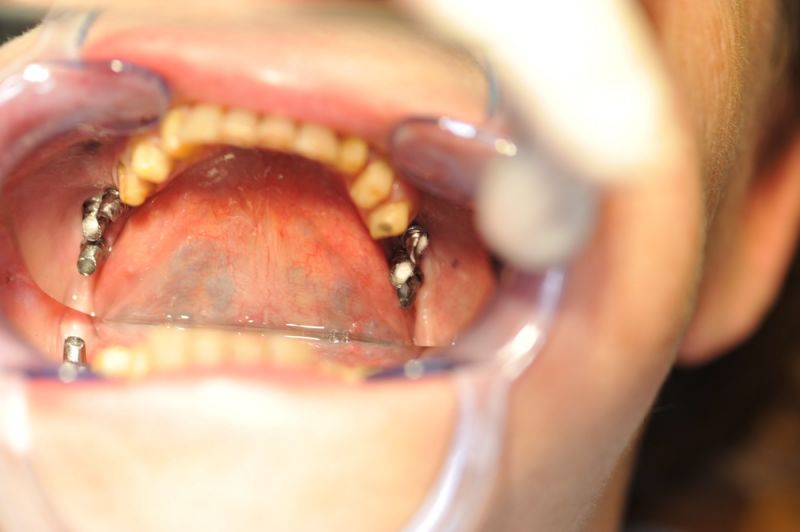

Es war eine Kombination aus Schmerzen bis an die Suizidgrenze, beschränkten wirtschaftlichen Möglichkeiten, sehr stark eingeschränkten Möglichkeiten der für Implantate zur Verfügung stehenden Knochenverhältnisse in einem stark atrophierten Unterkieferseitenzahnbereich und zudem dann auch noch durch auftretenden Problemen bei der Implantatinsertion und nachfolgenden Versorgung der Implantate.

Die Problematik der Implantatversorgungen kann man in einer Analogie folgendermaßen darstellen. Die räumlich beengten Zustände gleichen dem Tanz eines Paares auf einer Briefmarke, und der gleichzeitigen Schritt- und Fusshaltung, dass beim Tanzen die Schuhe geputzt werden können!